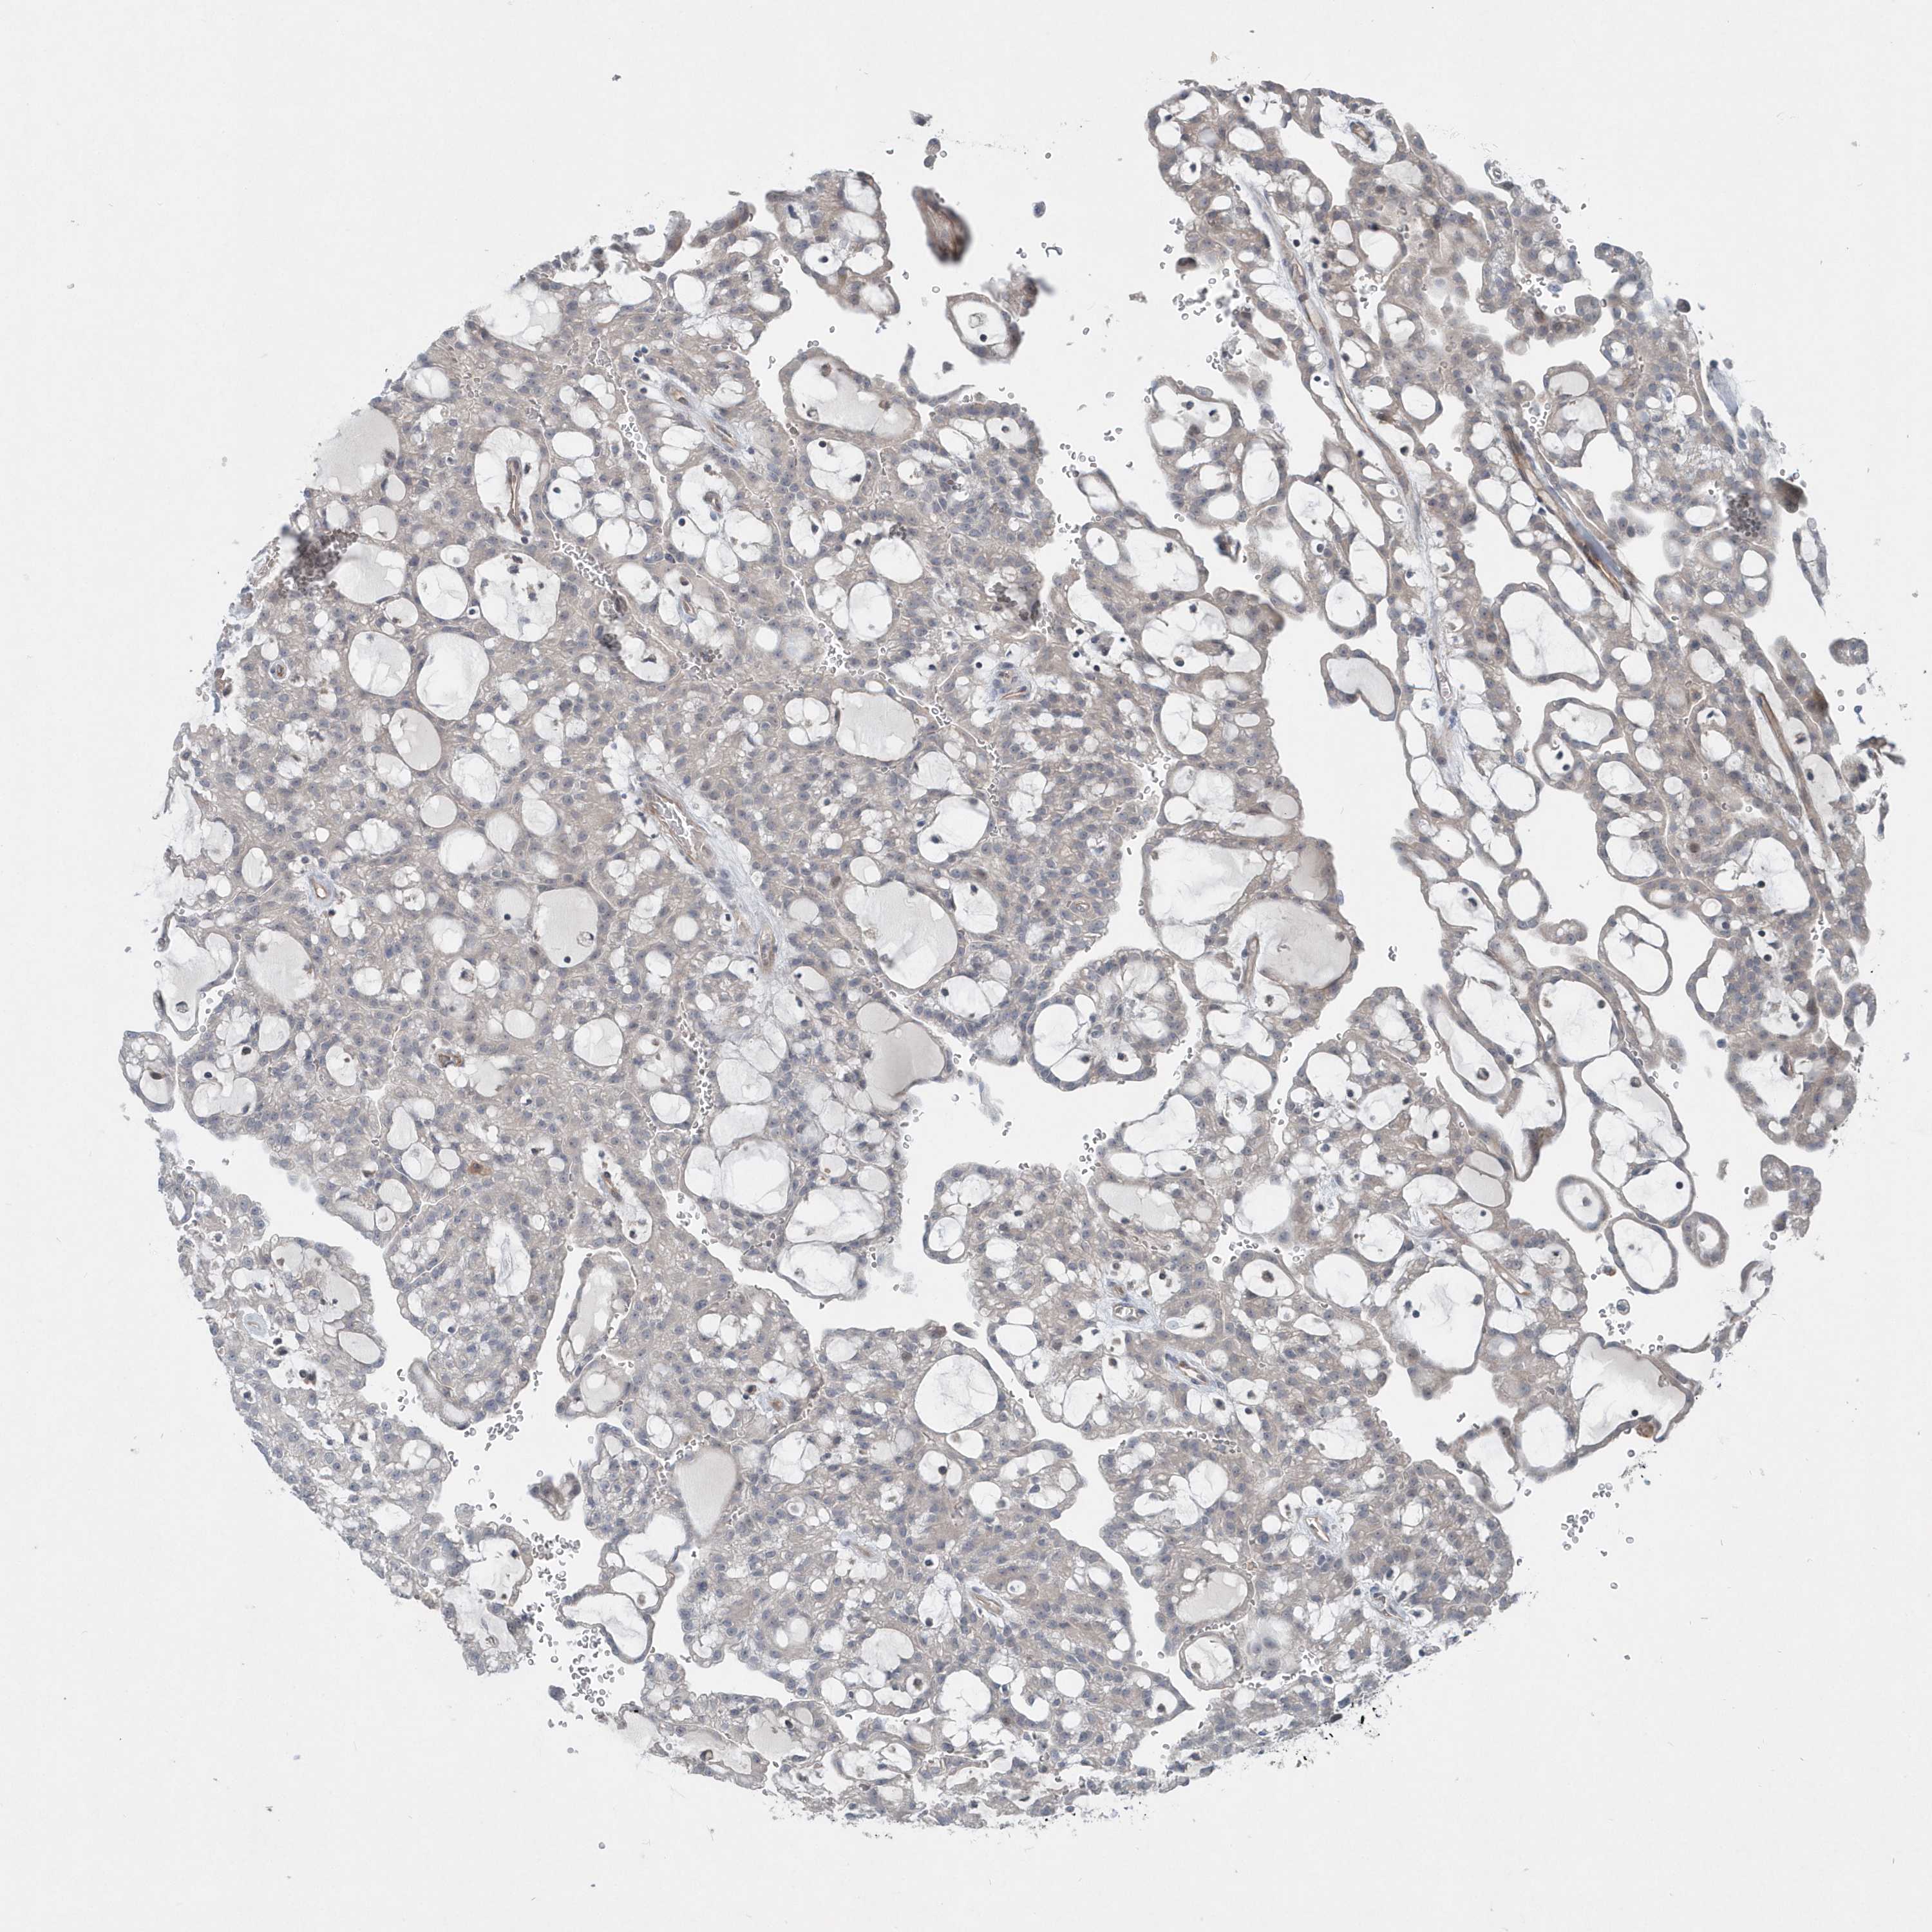

KIDNEY RENAL CLEAR CELL CARCINOMA (TCGA) - Interactive survival scatter ploti

The Survival Scatter plot shows the clinical status (i.e. dead or alive) for all individuals in the patient cohort, based on the same data that underlies the corresponding Kaplan-Meier plots. Patients that are alive at last time for follow-up are shown in blue and patients who have died during the study are shown in red.

The x-axis shows the expression levels (FPKM) of the investigated gene in the tumor tissue at the time of diagnosis. The y-axis shows the follow-up time after diagnosis (years). Both axes are complimented with kernel density curves demonstrating the data density over the axes. The top density plot shows the expression levels (FPKM) distribution among dead (red) and alive patients (blue). The right density plot shows the data density of the survived years of dead patients with high and low expression levels respectively, stratified using the cutoff indicated by the vertical dashed line through the Survival Scatter plot. This cutoff is automatically defined based on the FPKM cutoff that minimizes the p-score. The cutoff can be changed by dragging the vertical line or by entering a cutoff value in the square labeled "Current cut-off".

Under the Survival Scatter plot the p-score landscape (black curve; left axis) is shown together with dead median separation (red curve; right axis). Dead median separation is the difference in median mRNA expression between patients who have died with high and low expression, respectively. It is calculated as follows: median FPKM expression of dead patients with high expression - median FPKM expression of dead patients with low expression. This is intended to aid the user in visually exploring custom cutoffs and the associated p-scores and dead median separation.

Individual patient data is displayed and can be filtered by clicking on one or more of the category buttons on the top of the page. Categories describing expression level and patient information include: high, low, alive, dead, female, male and tumor stages. The scale of the x-axis can be toggled between linear and log-scale by clicking on the "x log" button. Mouse-over function shows TCGA ID, patient information and mRNA expression (FPKM) for each patient.

& Survival analysisi

Kaplan-Meier plots summarize results from analysis of correlation between mRNA expression level and patient survival. Patients were divided based on level of expression into one of the two groups "low" (under cut off) or "high" (over cut off). X-axis shows time for survival (years) and y-axis shows the probability of survival, where 1.0 corresponds to 100 percent.

MCC is validated prognostic, high expression is favorable in Kidney Renal Clear Cell Carcinoma (TCGA)

Best expression cut offi

: 6.25

P scorei

N/A

5-year survival highi

For melanoma and glioma, 3-year survival is shown.

5-year survival lowi

TCGA RNA samplesi

RNA-seq data is reported as average FPKM (number Fragments Per Kilobase of exon per Million reads), generated by the The Cancer Genome Atlas (TCGA) .

Normal distribution across the dataset is visualized with box plots, shown as median and 25th and 75th percentiles. Points are displayed as outliers if they are above or below 1.5 times the interquartile range. FPKM values of the individual samples are presented next to the box plot.

Average pTPM 5.7

Number of samples 521